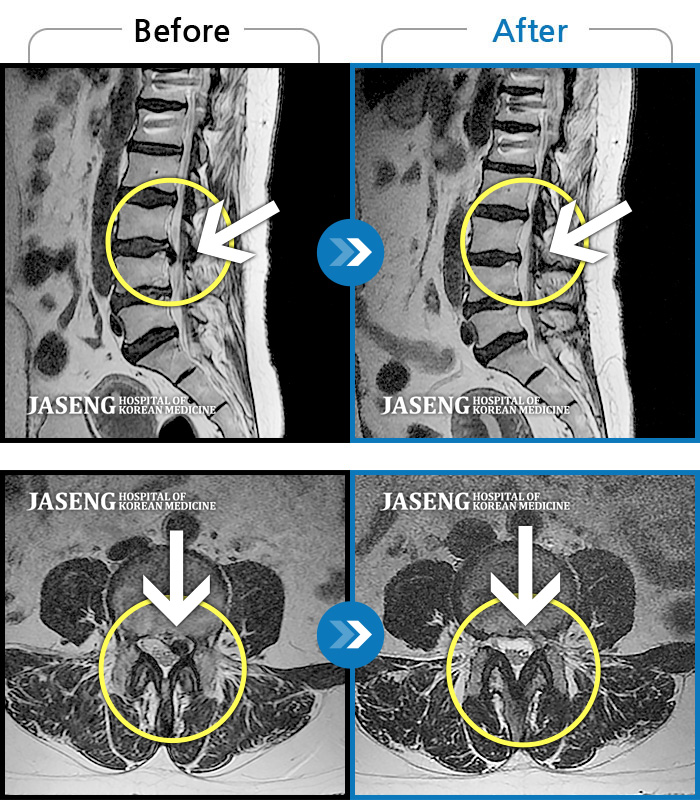

25년 1월 허리통증이 시작되고 잠을 잘수도없고 걸을 수 없을만큼의 상태가 되었을때 다시 김태용 원장님께 진료를 받고 예전 허리수술의(4번5번)(3번4번)디스크탈출증 재발과 협착증의 진단을 받고 지금까지 기나긴 여정의 입원 치료를 하며 곧 퇴원을 앞두고 있습니다.